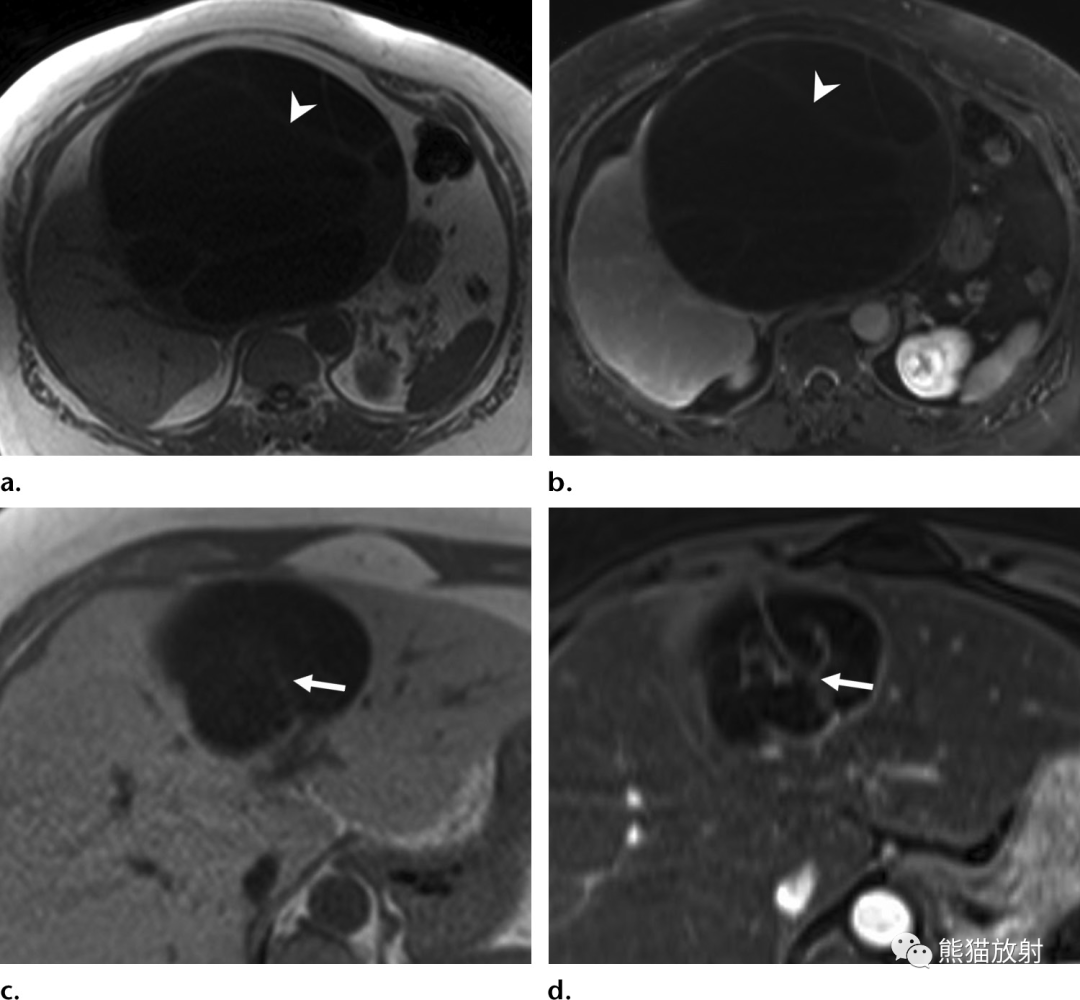

32岁 HIV/AIDS男性患者,细菌性紫癜,表现为发热。

(a)T1WI同相位图像显示肝右叶后段边界不清的等至轻度低信号结节(箭)。(b)脂肪饱和T2WI显示结节呈中高信号(箭),后方肝被膜下见数个较小结节(箭头)。(c)增强动脉早期图像显示结节周围不规则明显强化。(d)增强延迟期结节内部延迟强化,由于造影剂滞留在病灶内扩张的肝窦内,因此达到与周围肝静脉结构相似的信号强度。